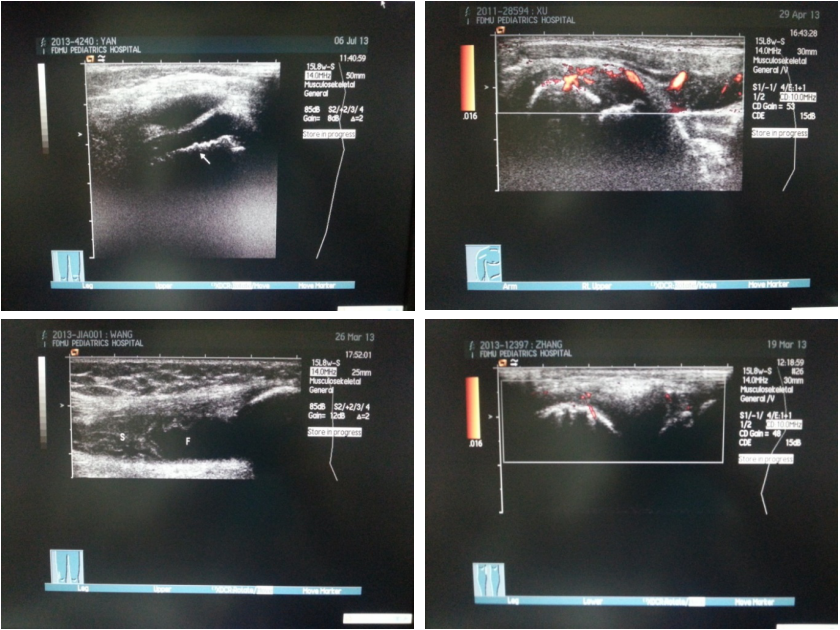

B超

不同影像学检查的优缺点